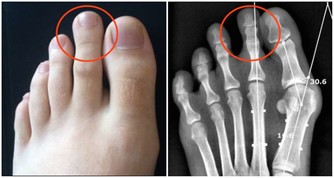

1、減緩胃灼熱

左側睡能緩解胃灼熱的症狀,而右側的側睡反而會讓症狀變得更糟糕。